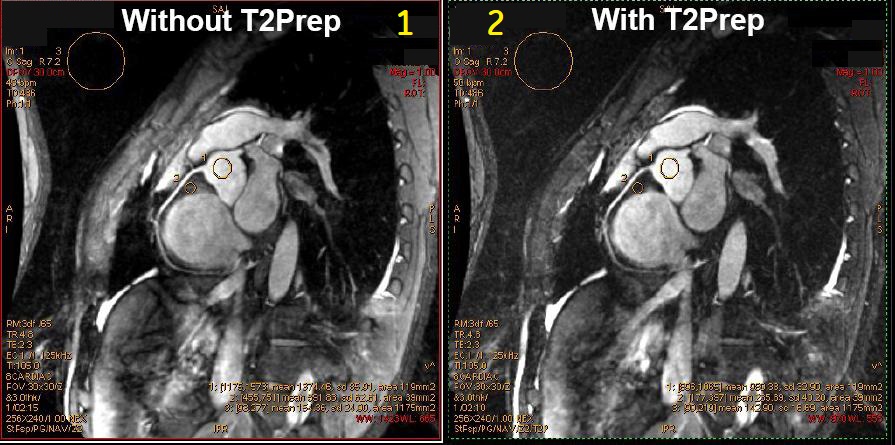

Figure 3. T2 Prep comparison

Table 3. Image legend Number Description 1 T2 Prep Imaging Option turned Off. 2 T2 Prep Imaging Option turned On. - MinFull TE and 1 NEX available with Slice Resolution User CV that reduces scan time and retains image sharpness